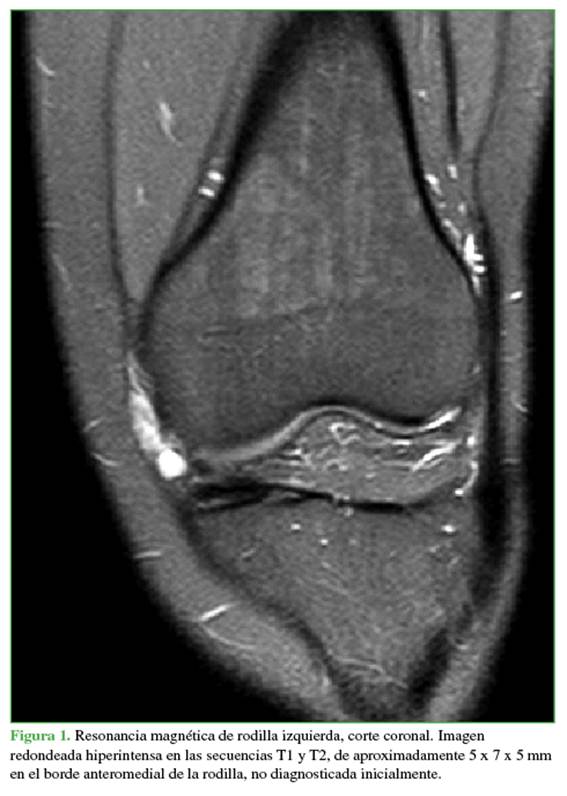

La revisión de esa RM reveló una imagen redondeada hiperintensa en las secuencias T1 y T2 de aproximadamente 5 x 7 x 5 mm en el borde anteromedial de la rodilla (Figura 1).

En ese momento, se solicitó el par radiográfico correspondiente, una ecografía Doppler y una RM. La radiografía no mostró particularidades. En la ecografía, la lesión fue informada como un “proceso nodular mixto sólido quístico con calcificación proximal, de aproximadamente 22 x 5 mm, impresionando estar en la relación con la articulación femororotuliana, sugestivo de origen sinovial” (Figura 2). En la RM, se visualizó la misma imagen ya descrita, pero ahora de 16 x 18 x 21 mm, también hiperintensa en las secuencias T1 y T2 (Figura 3).